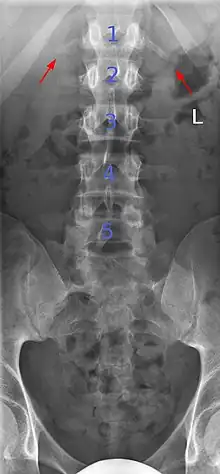

Several congenital block vertebrae in the transition from the thoracic to the lumbar spine and hemivertebrae.

Congenital block vertebra in the lumbar spine (partial vertebrae 3 and 4). The rear portion of the disc still exists.